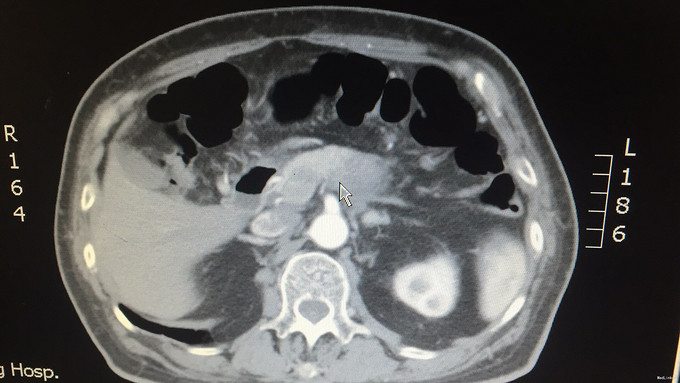

查体:腹部平坦,未见腹壁紧张及腹壁静脉曲张,无肠型及蠕动波;腹平软,无压痛、反跳痛、肌紧张等,未及明显异常,肝区无叩击痛,移动性浊音(—),肠鸣音4次/分,无增强或减弱。振水音(+)。 辅查:外院血癌胚抗原:41.39ng/ml;外院上腹部MRI增强:胰腺体尾部占位,考虑恶性,胰腺癌可能性大。我院上腹部CT平扫+增强:胰腺体部以远前后径约2.6cm,平扫CT值约50HU,增强后动脉期及门脉期CT值约68HU。胰胃间隙及胰后间隙稍模糊,可见数个淋巴结影,最大者长径约9.2cm。左侧肾上腺后支稍饱满,似可见一长径约1cm稍高密度影。[印象]:1.胰腺体尾部占位,恶性可能;2.腹腔内及腹膜后数个淋巴结;3.左侧肾上腺饱满,清结合临床。我院肿瘤指标检查:CA19-9:4.13U/ml,CEA:34.91U/ml,AFP:5.40U/ml。